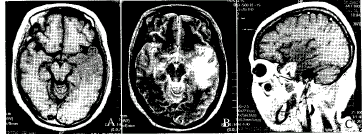

附图 放射性脑病MRI表现

A:平扫轴位T1WI双侧颞叶片状长T1信号,境界欠清.B:平扫轴位T2WI上述病灶呈长T2信号.C:增强矢状位T1WI上述病灶呈不规则环状强化.

MRI表现 (1)病灶部位:病灶分布多以照射区为中心,脑白质受累为主,位于颞叶、脑干及小脑。累及一侧或双侧颞叶7例(26.9%),桥脑7例(26.9%),中脑4例(15.4%),延髓6例(23.1%),小脑2例(7.7%)。(2)病灶形态:多呈不规则形大片状或斑片状、椭圆形或圆形。(3)病灶信号改变:T1加权成像(T1WI)病灶信号强度为低信号或等信号(图A)。其中1例左颞叶低信号灶内见囊状水样信号。T2加权成像(T2WI)病灶信号强度均为高信号(图B)。(4)增强效应:9例静脉注射Gd-DTPA增强后,7例病灶可见环行强化或病灶不均匀强化影(图C),2例无强化。(5)占位效应:本组2例单侧病变显示明显占位效应。